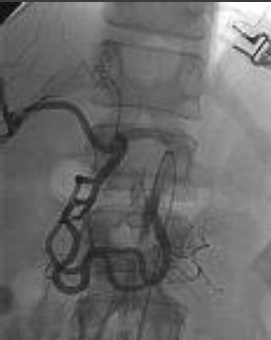

胰十二指肠动脉瘤占内脏动脉瘤2%。主要原因包括动脉硬化,腹腔动脉狭窄等疾病,后者是由于胰腺动脉弓的高血流状态(Sutton and Lawton 1973)。假性动脉瘤主要由于胰腺炎、创伤和感染(Suzuki et al. CVIR 2008;31:1082-1087)。 腹腔动脉闭塞导致胰腺血管弓

腹腔动脉闭塞导致胰腺血管弓的高血流状态致使胰腺动脉明显增粗 |

Suzuki 等人报告7例CT证实破裂动脉瘤病人,平均直径0.6mm。破裂与大小没有直接联系,18%的破裂动脉瘤<1cm。一般推荐在发现时就进行血管内治疗,但要考虑解剖情况和技术上的困难。